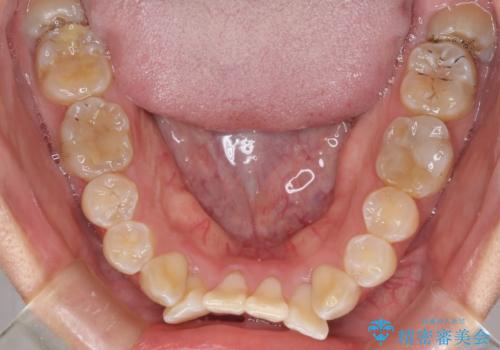

- 上下の前歯のでこぼこを気にして来院された患者様です。

途中転勤や出産があり、通院できない期間が長くありましたが、無事に歯列を整えることができました。